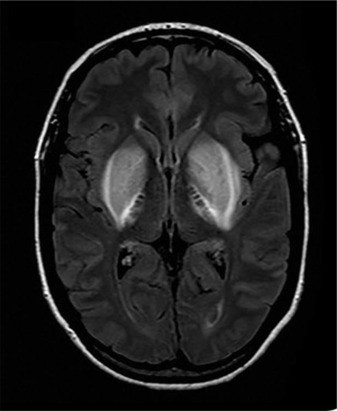

TAG: kerusakan otak

Ada 9 Artikel yang mempunyai tag "Kerusakan Otak"